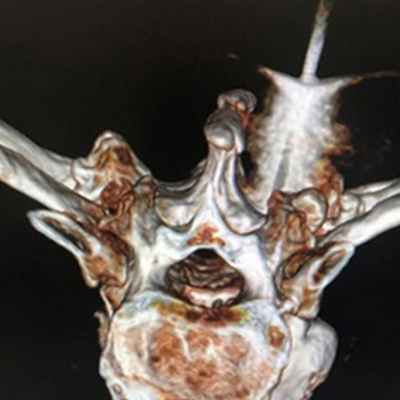

Наиболее значимыми рентгенологическими признаками злокачественной опухоли являются:

- наличие очага разрушения (деструкции) кости;

- наличие периостальной реакции в виде характерного козырька, длинных нитеобразных спикул, расположенных перпендикулярно по отношению к кости, появление рядом с пораженной костью, а также мягкотканного компонента с участками обызвествления.

Обязательным является выполнение рентгенографии всей пораженной кости, а также КТ или МРТ. Эти исследования могут повторяться в процессе химиотерапии для оценки ее эффективности.